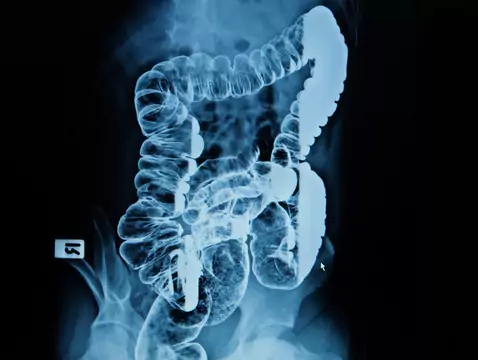

Radiotherapy is one of the most commonly used methods in the treatment of malignant tumours. Nearly 60% of patients are treated using this method. Radiotherapy can be used as a stand-alone form of...